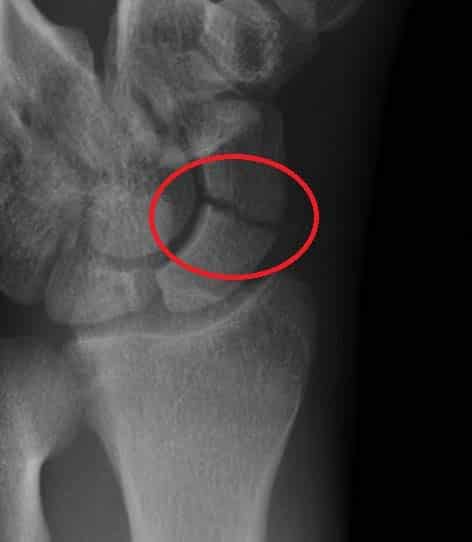

The anatomical snuffbox (also known as the radial fossa), is a triangular depression found on the lateral aspect of the dorsum of the hand. It is located at the level of the carpal bones, and best seen when the thumb is extended. In the past, this depression was used to hold snuff (ground tobacco) before inhaling via the nose – hence it was given the name ‘snuffbox’. In this article, we shall look at the anatomy of the anatomical snuffbox – its borders, contents, and any clinical correlations. By TeachMeSeries Ltd (2025) Fig 1The left anatomical snuffbox. Note its lateral position on the dorsum of the hand Pro Feature - 3D Model You've Discovered a Pro Feature Access our 3D Model Library Explore, cut, dissect, annotate and manipulate our 3D models to visualise anatomy in a dynamic, interactive way. Learn More Borders As the snuffbox is triangularly shaped, it has three borders, a floor, and a roof: Ulnar (medial) border: Tendon of the extensor pollicis longus. Radial (lateral) border: Tendons of the extensor pollicis brevis and abductor pollicis longus. Proximal border: Styloid process of the radius. Floor: Carpal bones; scaphoid and trapezium. Roof: Skin. (Note: The terms medial and lateral are used in the context of the anatomical position, where the forearm is supinated. Take care when describing these borders, as when observing a patient’s anatomical snuffbox, the forearm is usually pronated). It is important to note that the tendons of the muscles form the borders, not the muscles themselves. By TeachMeSeries Ltd (2025) Fig 2The tendinous borders of the anatomical snuffbox. Pro Feature - Dissection Images Borders and contents of the anatomical snuffbox Borders and contents of the anatomical snuffbox You've Discovered a Pro Feature Access our Dissection Image Library Enhance your understanding with high-resolution dissection images showcasing real-life anatomy. Learn More Contents The main contents of the anatomical snuffbox are the radial artery, a branch of the radial nerve, and the cephalic vein: Radial artery – crosses the floor of the anatomical snuffbox, then turns medially and travels between the heads of the adductor pollicis muscle. The radial pulse can be palpated in some individuals by placing two fingers on the proximal portion of the anatomical snuffbox. Superficial branch of the radial nerve – found in the skin and subcutaneous tissue of the anatomical snuffbox. It innervates the dorsal surface of the lateral three and half digits, and the associated area on the back of the hand. Cephalic vein – arises from the dorsal venous network of the hand and crosses the anatomical snuffbox to travel up the anterolateral aspect of the forearm. By TeachMeSeries Ltd (2025) Fig 3Veins of the dorsum of the hand. Cephalic vein highlighted. Clinical Relevance Scaphoid Fracture The scaphoid bone of the hand is the most commonly fractured carpal bone – typically by falling on an oustretched hand (FOOSH). In a fracture of the scaphoid, the characteristic clinical feature is pain and tenderness in the anatomical snuffbox. The scaphoid is at particular risk of avascular necrosis after fracture because of its so-called ‘retrograde blood supply’ which enters at its distal end. This means that a fracture to the middle (or ‘waist’) of the scaphoid may interrupt the blood supply to the proximal part of the scaphoid bone rendering it avascular. Patients with a missed scaphoid fracture are likely to develop osteoarthritis of the wrist in later life. By Gilo1969 (Own work) [CC-BY-SA-3.0], via Wikimedia Commons Fig 4Radiograph of a scaphoid fracture. Adapted from work by Iiibalesiii [CC BY-SA 4.0] Fig 5The blood supply to the scaphoid bone runs from distal to proximal. Do you think you’re ready? Take the quiz below Pro Feature - Quiz The Anatomical Snuffbox Question 1 of 3 Submitting... Skip Next Rate question: You scored 0% Skipped: 0/3 1800 More Questions Available Upgrade to TeachMeAnatomy Pro Challenge yourself with over 1800 multiple-choice questions to reinforce learning Learn More Rate This Article